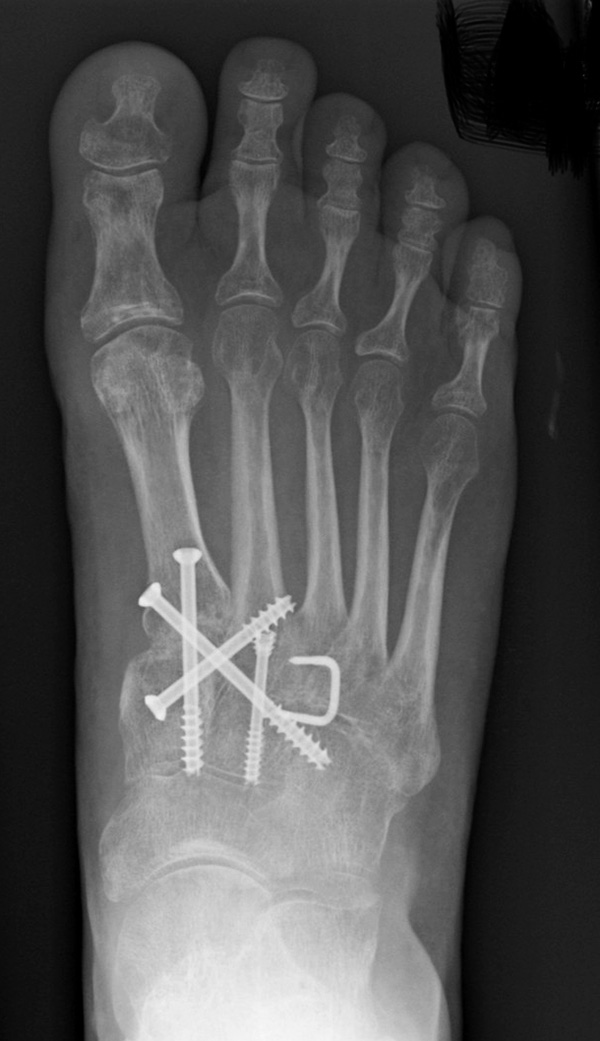

Wird die Entscheidung zur Arthrodese gefällt, sollten nur Gelenke mit einer symptomatischen Arthrose versteift werden. Meist genügt die Arthrodese der TMT-1 bis 3-Gelenke. Die Arthrodese kann mit Schrauben oder dorsalen Platten durchgeführt werden. Die betroffenen Gelenkflächen werden entknorpelt und das Gelenk mit einer Zugschraubentechnik oder einer dorsalen Platte stabilisiert (Abb. 19-22) 25 (Richter 2002; Richter 2007). Einige Autoren befürworten eine primäre Arthrodese auch bei rein ligamentären Verletzungen mit multidirektionaler Instabilität, da diese eine schlechte Heilungstendenz aufweisen und häufiger zu Korrekturverlust neigen 3617112.

Zum Lesen der Bildbeschreibung und zur Vollansicht bitte die Bilder anklicken.